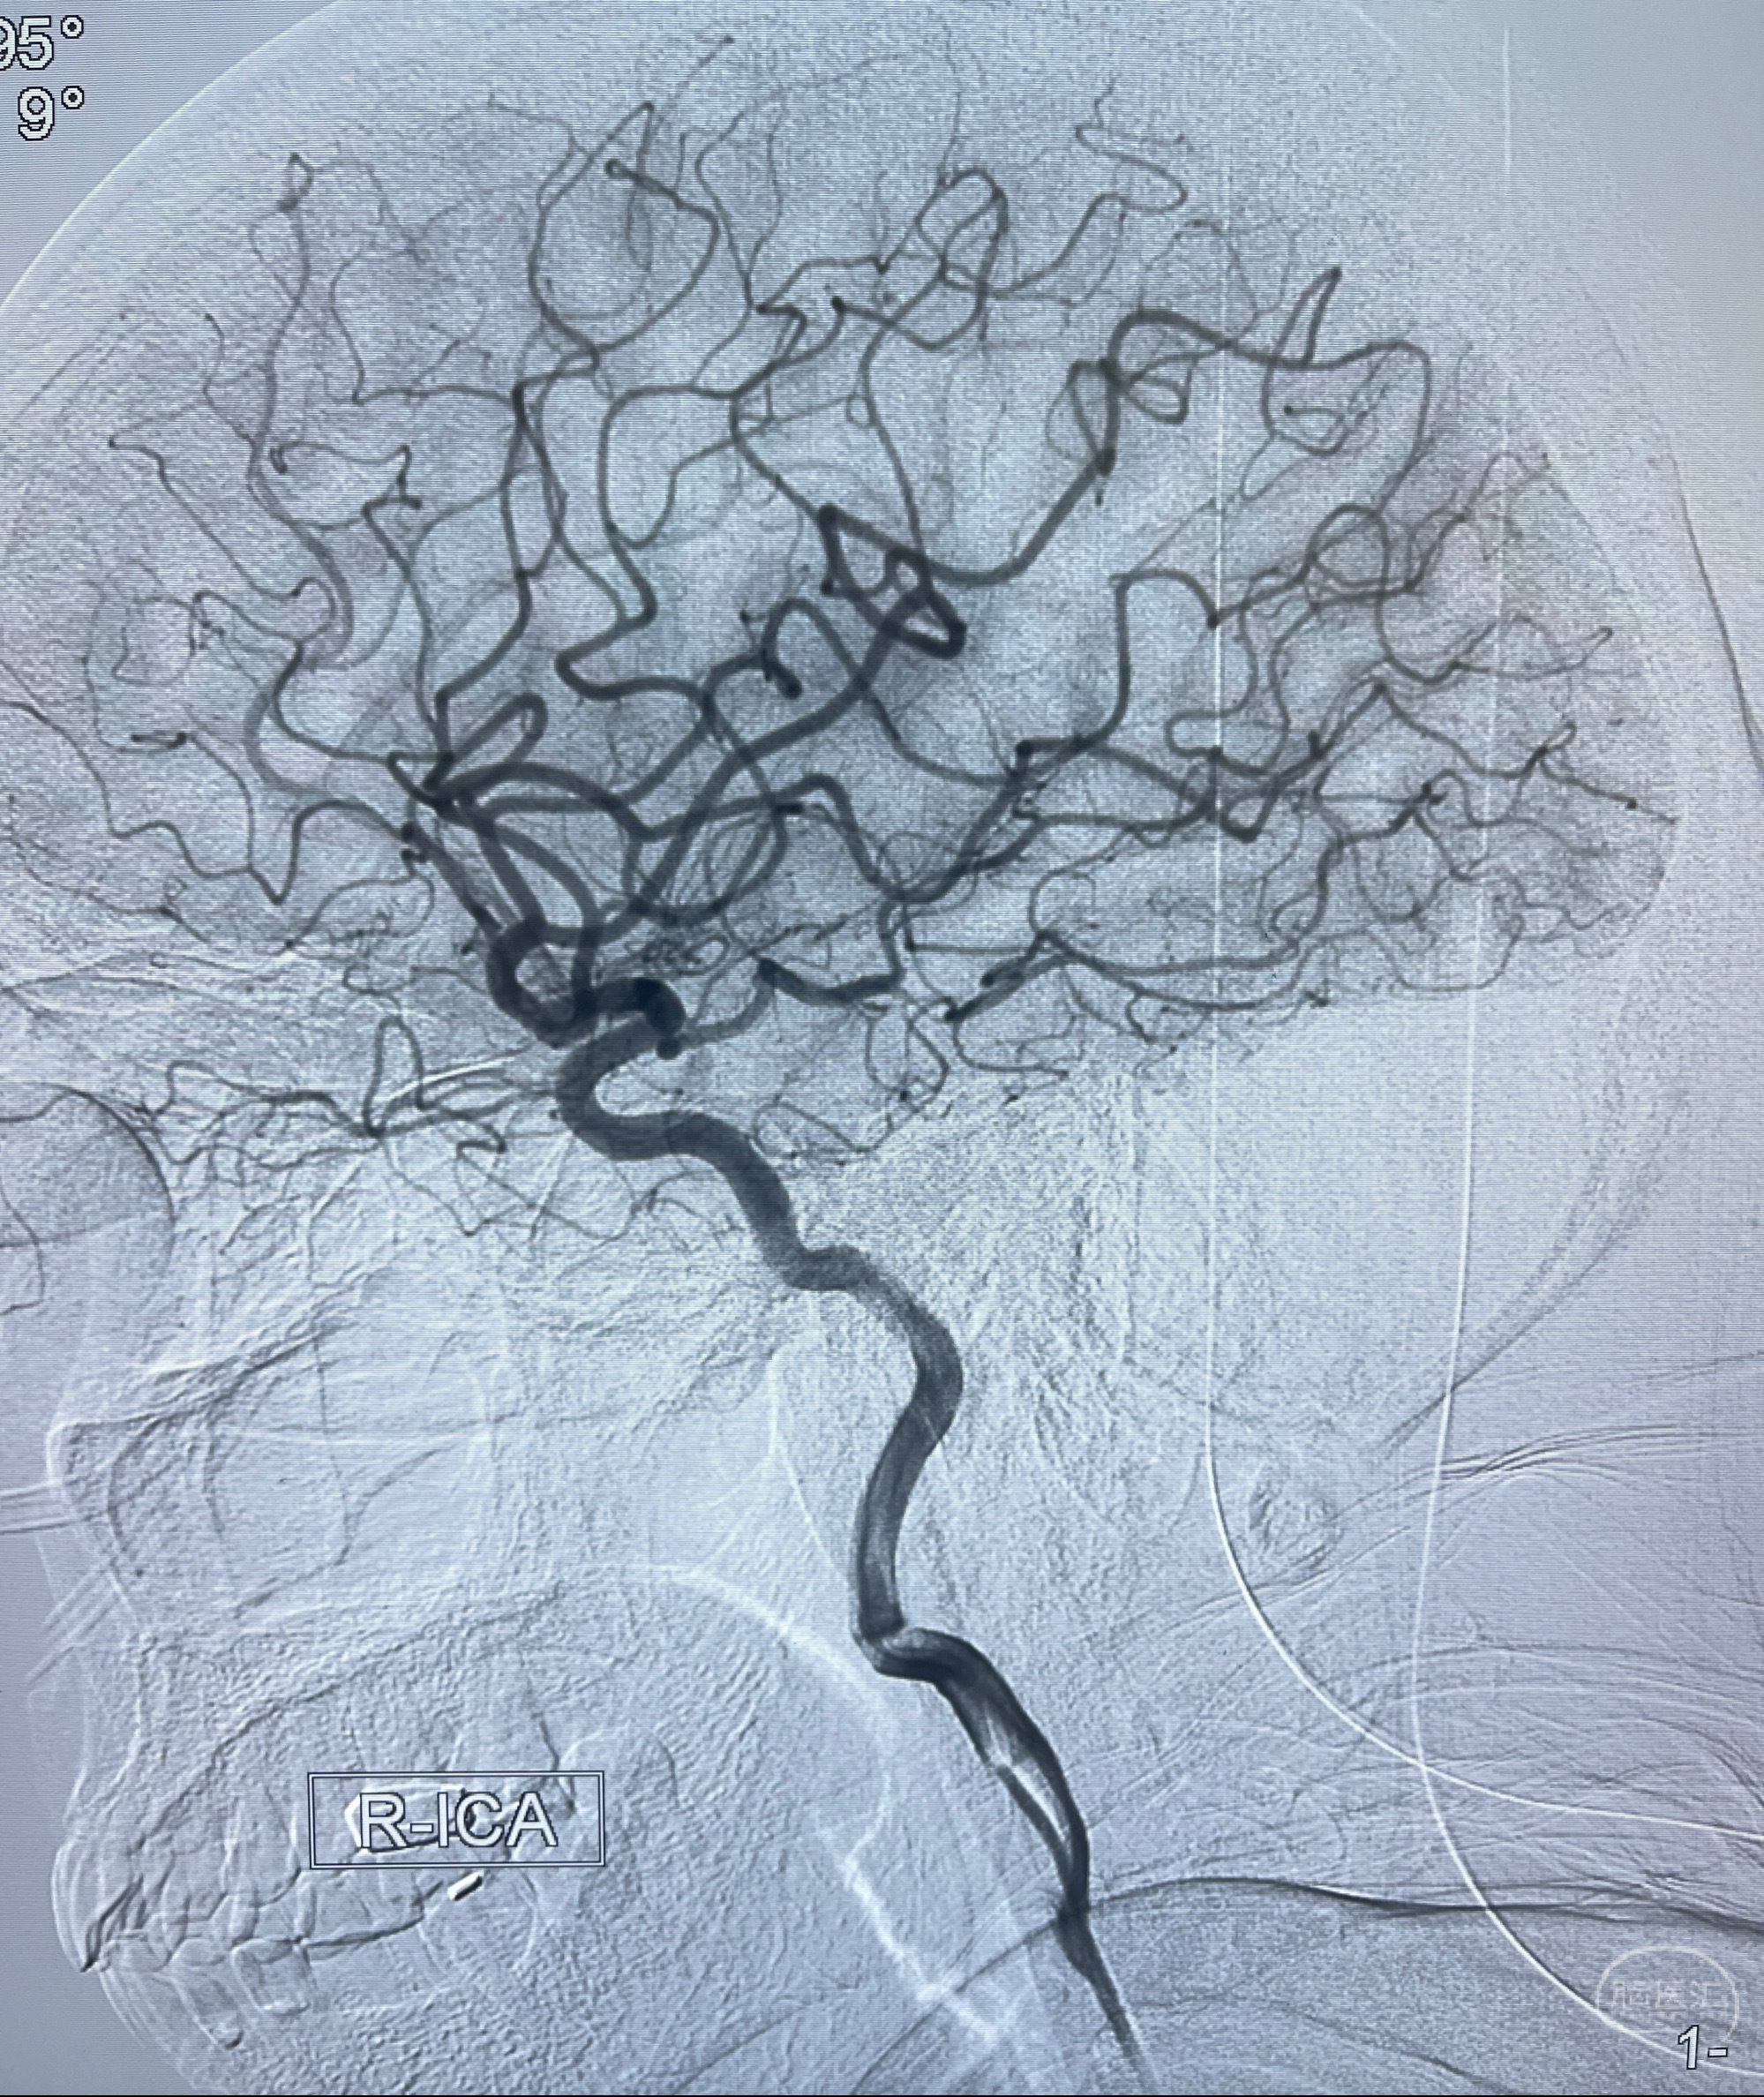

2023-02-02 沛县人民医院 头颅CTA:大脑动脉环发育变异,头颈部动脉粥样硬化,双侧颈内动脉及椎动脉颅内段多发狭窄;

1.双侧脑动脉狭窄

2.腔隙性脑梗死

2023-02-15DSA